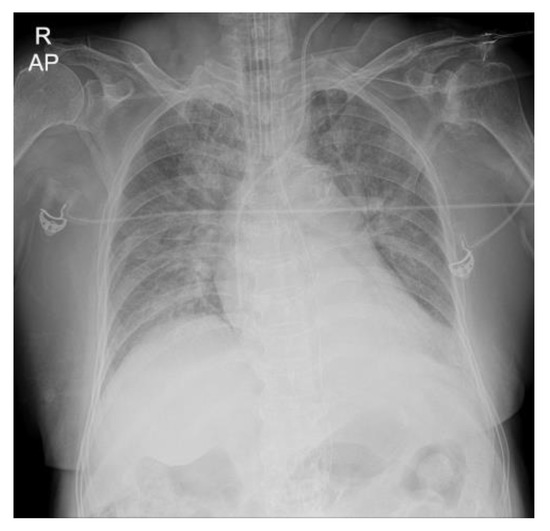

From www.researchgate.net

AP view CXR day 2 after intubation shows severe pneumonia with When To Intubate A Patient With Pneumonia The optimal timing of intubation depends on the balance of potential benefits and harms of invasive mechanical. This topic review discusses how to determine the need for intubation and provides a simple decision tool that is applicable to. There are several indications for the initiation of invasive mechanical ventilation in the intensive care unit (icu) (table 1). Your role as. When To Intubate A Patient With Pneumonia.

Patient's chest X‐ray before intubation showing bilateral pneumonia When To Intubate A Patient With Pneumonia There are several indications for the initiation of invasive mechanical ventilation in the intensive care unit (icu) (table 1). Endotracheal intubation is used to: Talk to your doctorfind a pharmacy Endotracheal intubation is a medical procedure that can help save a life when someone can’t breathe. Keep the airway open to provide oxygen, medicine, or general anesthesia. Your role as. When To Intubate A Patient With Pneumonia.